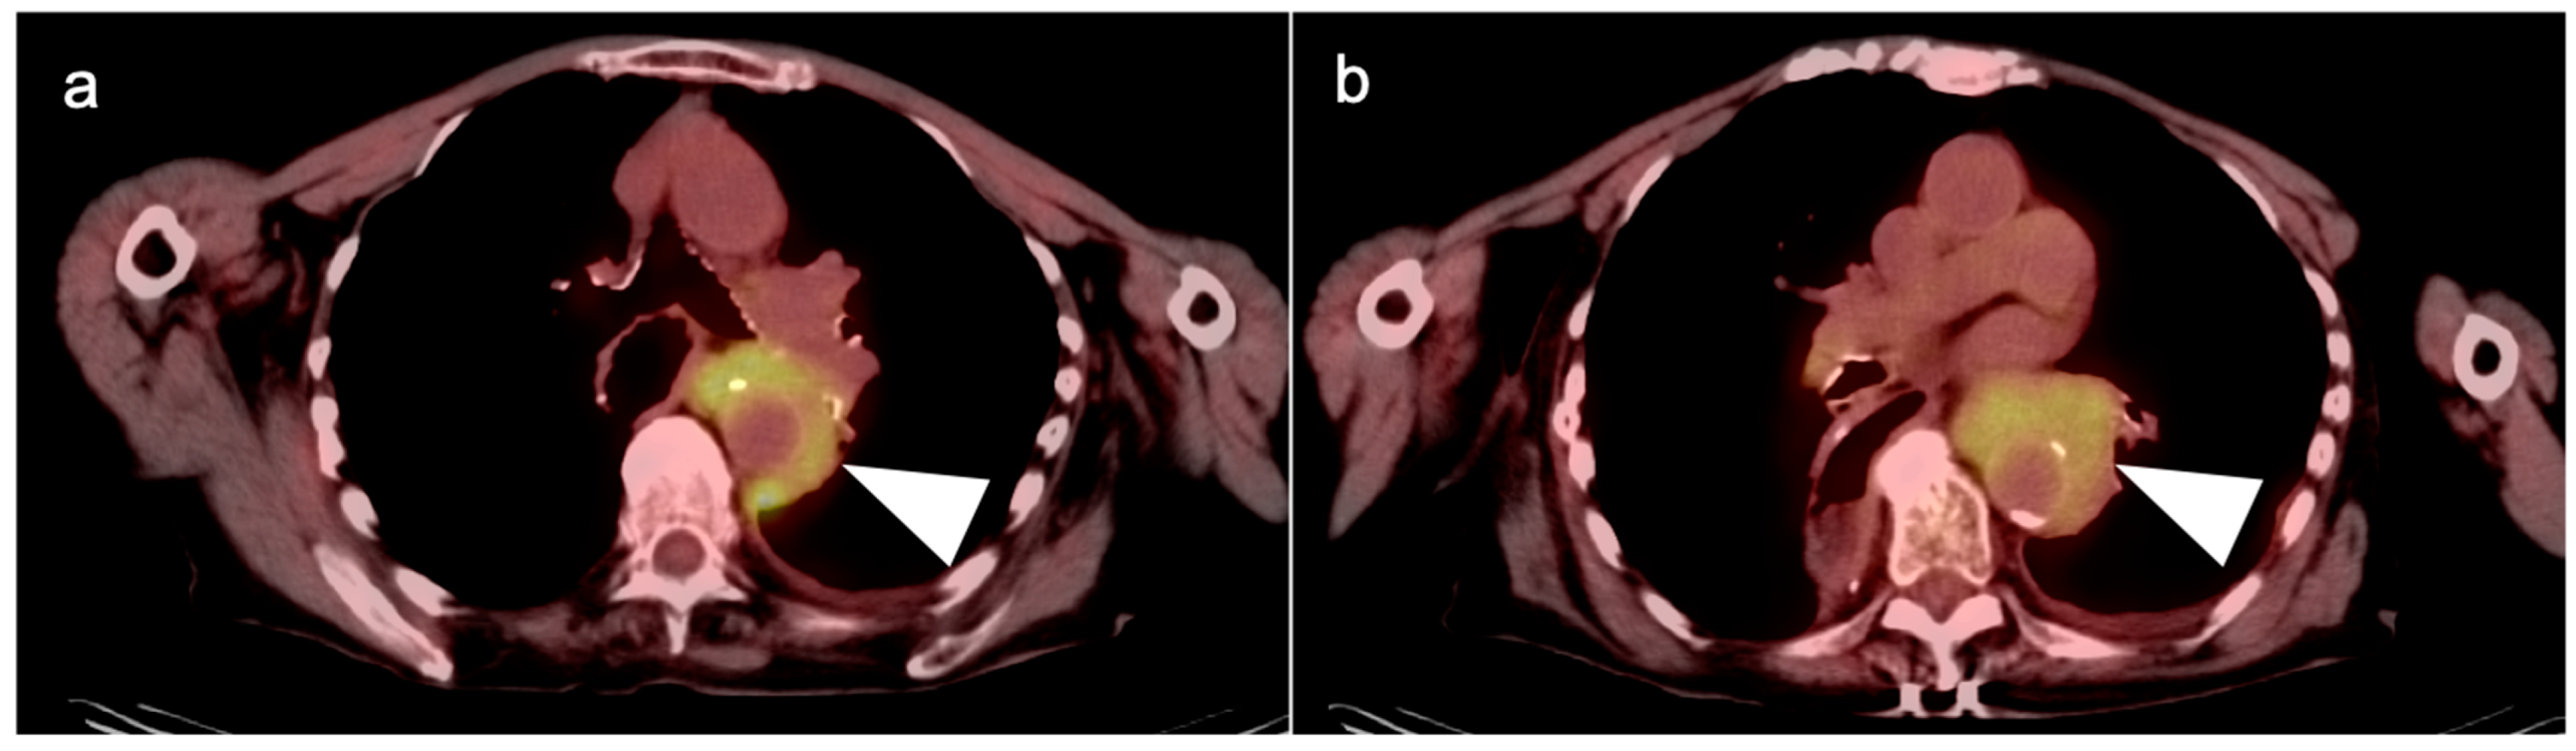

7. Adrenal Cancer